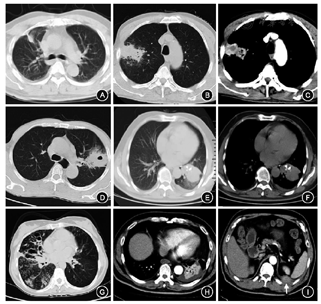

1例(3.3%)肺癌患者表现为气管隆突下、左主支气管内新生物阻塞影致左肺不张,余病灶分布见表1;影像学表现为不规则结节灶4例(13.3%)、肿块19例(63.3%),边界均不清,其中6例伴有毛刺征,9例病灶周围伴有磨玻璃样或斑片状渗出;存在肺实变表现8例(26.7%),其中1例伴有左侧第11/12后肋间隙肿块伴明显强化影;肺不张7例(23.3%);蜂窝状、囊柱状支气管扩张伴渗出病灶4例(13.3%);病灶中存在低密度灶共12例(40.0%),空洞或空泡样病变6例(20.0%),钙化灶4例(13.3%)(其中2例为异物、1例为支气管结石);合并胸腔积液6例(20.0%),胸膜牵拉8例(26.7%),胸膜增厚2例(6.7%),相应肺门或纵隔淋巴结肿大13例(43.3%)(图1)。3例(10.0%)患者行PET-CT检查,均显示病灶氟代脱氧葡萄糖代谢异常增高,提示肿瘤可能。

注:A.肺窗见右上叶前段结节状密度增高影,周围少许渗出病灶,胸膜牵拉;B.肺窗见右上肺片块状实变影,边界不清,周围散在渗出;C.增强窗见病灶内中心低密度灶,边缘强化明显,空泡征;D.肺窗见团片状肿块影,内见空洞影,边缘渗出病灶;E.肺窗见左肺下叶团片状实变影伴有肺不张;F.纵隔窗可见病灶内钙化灶,胸腔积液,气管镜证实钙化灶为支气管结石;G.肺窗见右肺囊状支气管扩张,树芽征;H.增强窗见左下肺实变影,胸腔积液;I.接H往腹部延伸见左侧第11/12后肋间隙肿块伴明显强化(箭头所示)